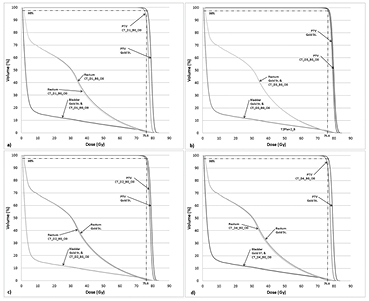

A similar trend was observed for the prostate PTV, where the magnitude of variation in target IMRT plan quality from the Gold St was ⩽2% on CT-based plans (table 6). The magnitude of variation in D95% was found to be −2.0%, −1.0%, 0.7%, and −1.8% for (CT_D1_B0_O0 to CT_D4_B0_O0) rED assignments, respectively. The variation in D5% was found to vary within the same range as D95%. The smallest and largest variations in D95% were found for the homogeneous water (CT_D3_B0_O0) and type1 rED assignments (CT_D1_B0_O0), respectively. The shapes of the DVHs for the prostate PTV are similar in shape for all four rED assignments (figure 2).

Figure 2. Prostate IMRT without 1.5 T field dose volume histogram (DVH) for a representative case (anonymized patient prost1) for the following different relative electron density assignments: (a) CT_D1_B0_O0; (b). CT_D2_B0_O0; (c) CT_D3_B0_O0 and (d) CT_D4_B0_O0. Note each panel depicts the DVHs of the PTV, rectum and bladder of the given rED plan together alongside the same structures from the gold standard (i.e. planning CT).

Standard image High-resolution imageThe variation in DVPs for the bladder, rectum and femoral heads was found to be ⩽6.0% for different rED CT-based plans (table 6), but the majority of differences in DVPs were <3.2%. For example, the bladder V70 and rectum Dmean was found to be no more than −0.3% and −1.9%, respectively, on CT-based plans (table 6). Both bladder and rectum DVHs are similar in shape for all CT-based plans with different rED assignments (figure 2). Homogeneous water rED assigned plans had variations larger than the Gold St, for example, the Dmax right femoral head was 6.1%. We chose to use the D1 rED assignment for the remaining parts of our analysis despite D3 yielding smaller variations in DVPs with respect to the Gold St in the pancreas case. The prostate case demonstrates the importance of assigning a reasonable value to the femoral heads in order to get boney DVP variations within 5% of the Gold St. The use of D1 assignment maintains some methodological consistency and could be important in certain situations (see discussion).

Representative pancreas and prostate case with magnetic field

When the TMF is present during dose recalculation but no re-optimization, the variation in pancreas and prostate DVPs does not exceed 3% (CT_D0_B1_O0 in tables 7(a) and (b)). This variation increases for the CT-based plans with a 1.5 T field present and type1 rED assignment (CT_D1_B1_O0) but does not exceed 3.6% for both pancreas and prostate IMRT plans. The effect of the presence of a 1.5 T TMF during dose calculation on the DVH results in curves with very similar shape (figure 3). However, a larger deviation between DVH curves is observed when forced rED assignment (type1) is used (figures 3(a)–(d) for the pancreas and prostate, respectively). The largest deviation in the prostate Dmax for the right femoral head (R-Fem Head in table 7) was 9.0% (an absolute dose difference of 24.6 Gy versus 22.3 Gy between CT_D0_B1_O0 and the Gold St, respectively).

Figure 3. Pancreas (panels (a) and (b)) and prostate (panels (c) and (d)) IMRT with 1.5 T field dose volume histogram for a representative case.